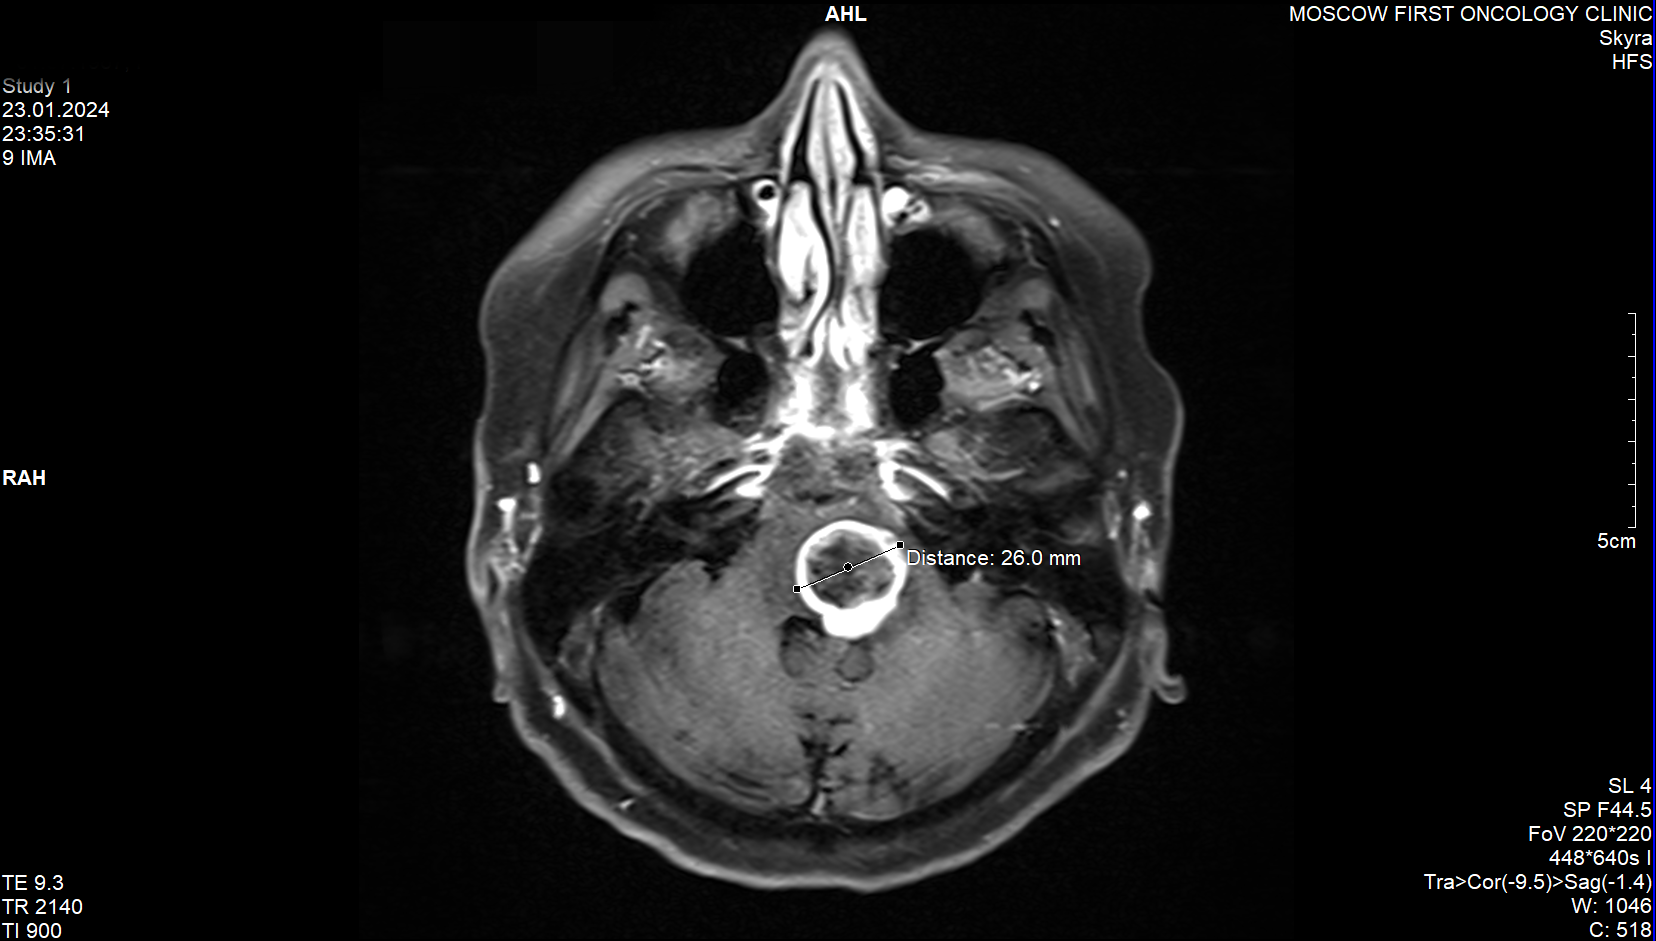

Вторая картинка - МРТ с отметкой, как я понимаю, повреждённых тканей. Удивительно, что такое большое пространство отмечено.

3,4я картинки - первое МРТ без специфических обозначений.

5,6я картинки - второе МРТ.

Как бы то ни было, заключение было следующим (текст сохранён): "По данным МРТ головного мозга с к/у от 24.01.24 пло сравнению с МРТ от 29.11.23- увеличение размеров очага в стволе головного мозга до 2, 6х2, 5х2, 4см (ранее-1.3х1.6х1.5см)... Рекомендована консультация онколога на предмет назначения лекарственной терапии (темозоломид± бевацизумаб). Врач-онколог. На предварительном заключении та-же фамилия значилась за "врач-радиотерапевт". Но это, наверное, не важно.